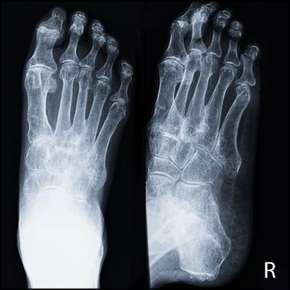

Overlapping, Underlapping Toes

Overlapping and underlapping toes are common podiatric conditions that can impact an individual's foot health and overall well-being. This comprehensive guide delves into the nuances of these toe abnormalities, exploring their definitions, causes, symptoms, potential complications, and available treatment